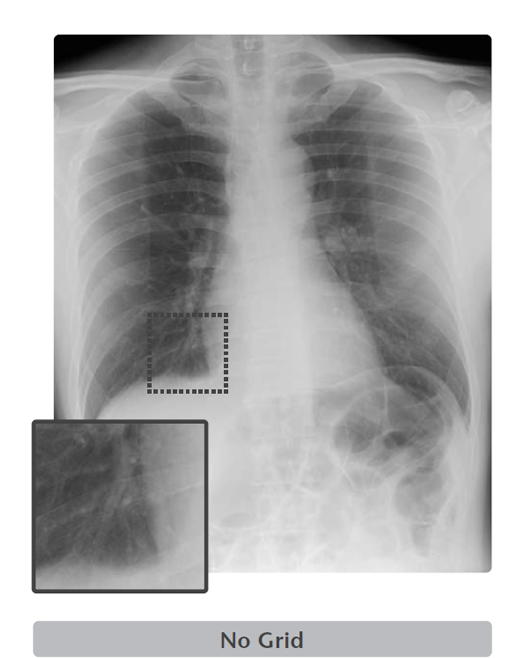

Virtual Grid

Image processing that remove the scatter X-rays from the digital radiography created without a physical grid.

Virtual Grid is an image processing software that corrects for the effects of scatter X-rays that otherwise reduce image contrast and clarity.

Without the need for physical grid, this software quickly predicts and then corrects for the effects of scatter X-rays, creating an improved image quality.

High quality images can be obtained under low dose conditions, thus reducing the amount of radiation does the patient receives

Virtual Grid selection

Virtual Grid allows setting of the grid ratio, number of grid lines and interspace material, and examinations using the appropriate grid conditions.

Just as for a physical grid, different Virtual Grid settings can be used, best suited for the different regions and exposure conditions.

Of course, as it is a virtually created grid, the grid type can be changed after an exposure.

Virtual Grid can be applied to all body parts. (Excluding breast imaging)